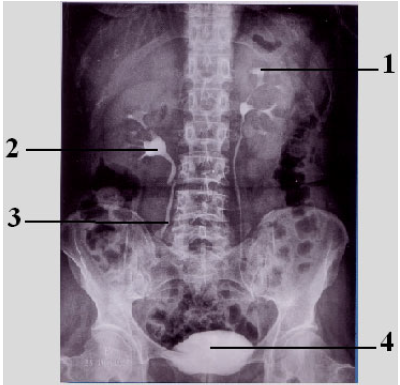

Observe a figura abaixo e, após, responda à questão.

Identifique as estruturas anatômicas assinaladas na figura e assinale a alternativa

correta.

1- pelve renal; 2- cálice renal; 3- ureter; 4- bexiga

1- cálice renal; 2- pelve renal; 3- ureter; 4- bexiga

1- cálice renal; 2- pelve renal; 3- uretra; 4- próstata

1- pelve renal; 2- cálice renal; 3- uretra; 4- próstata